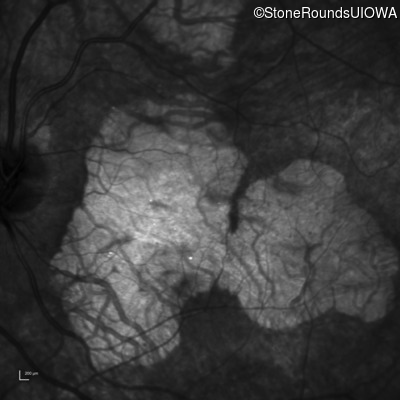

Infrared Fundus Photograph - Right - 20/20 -2 sc

Exemplar

Infrared Fundus Photograph - Left - 20/30 +1 sc